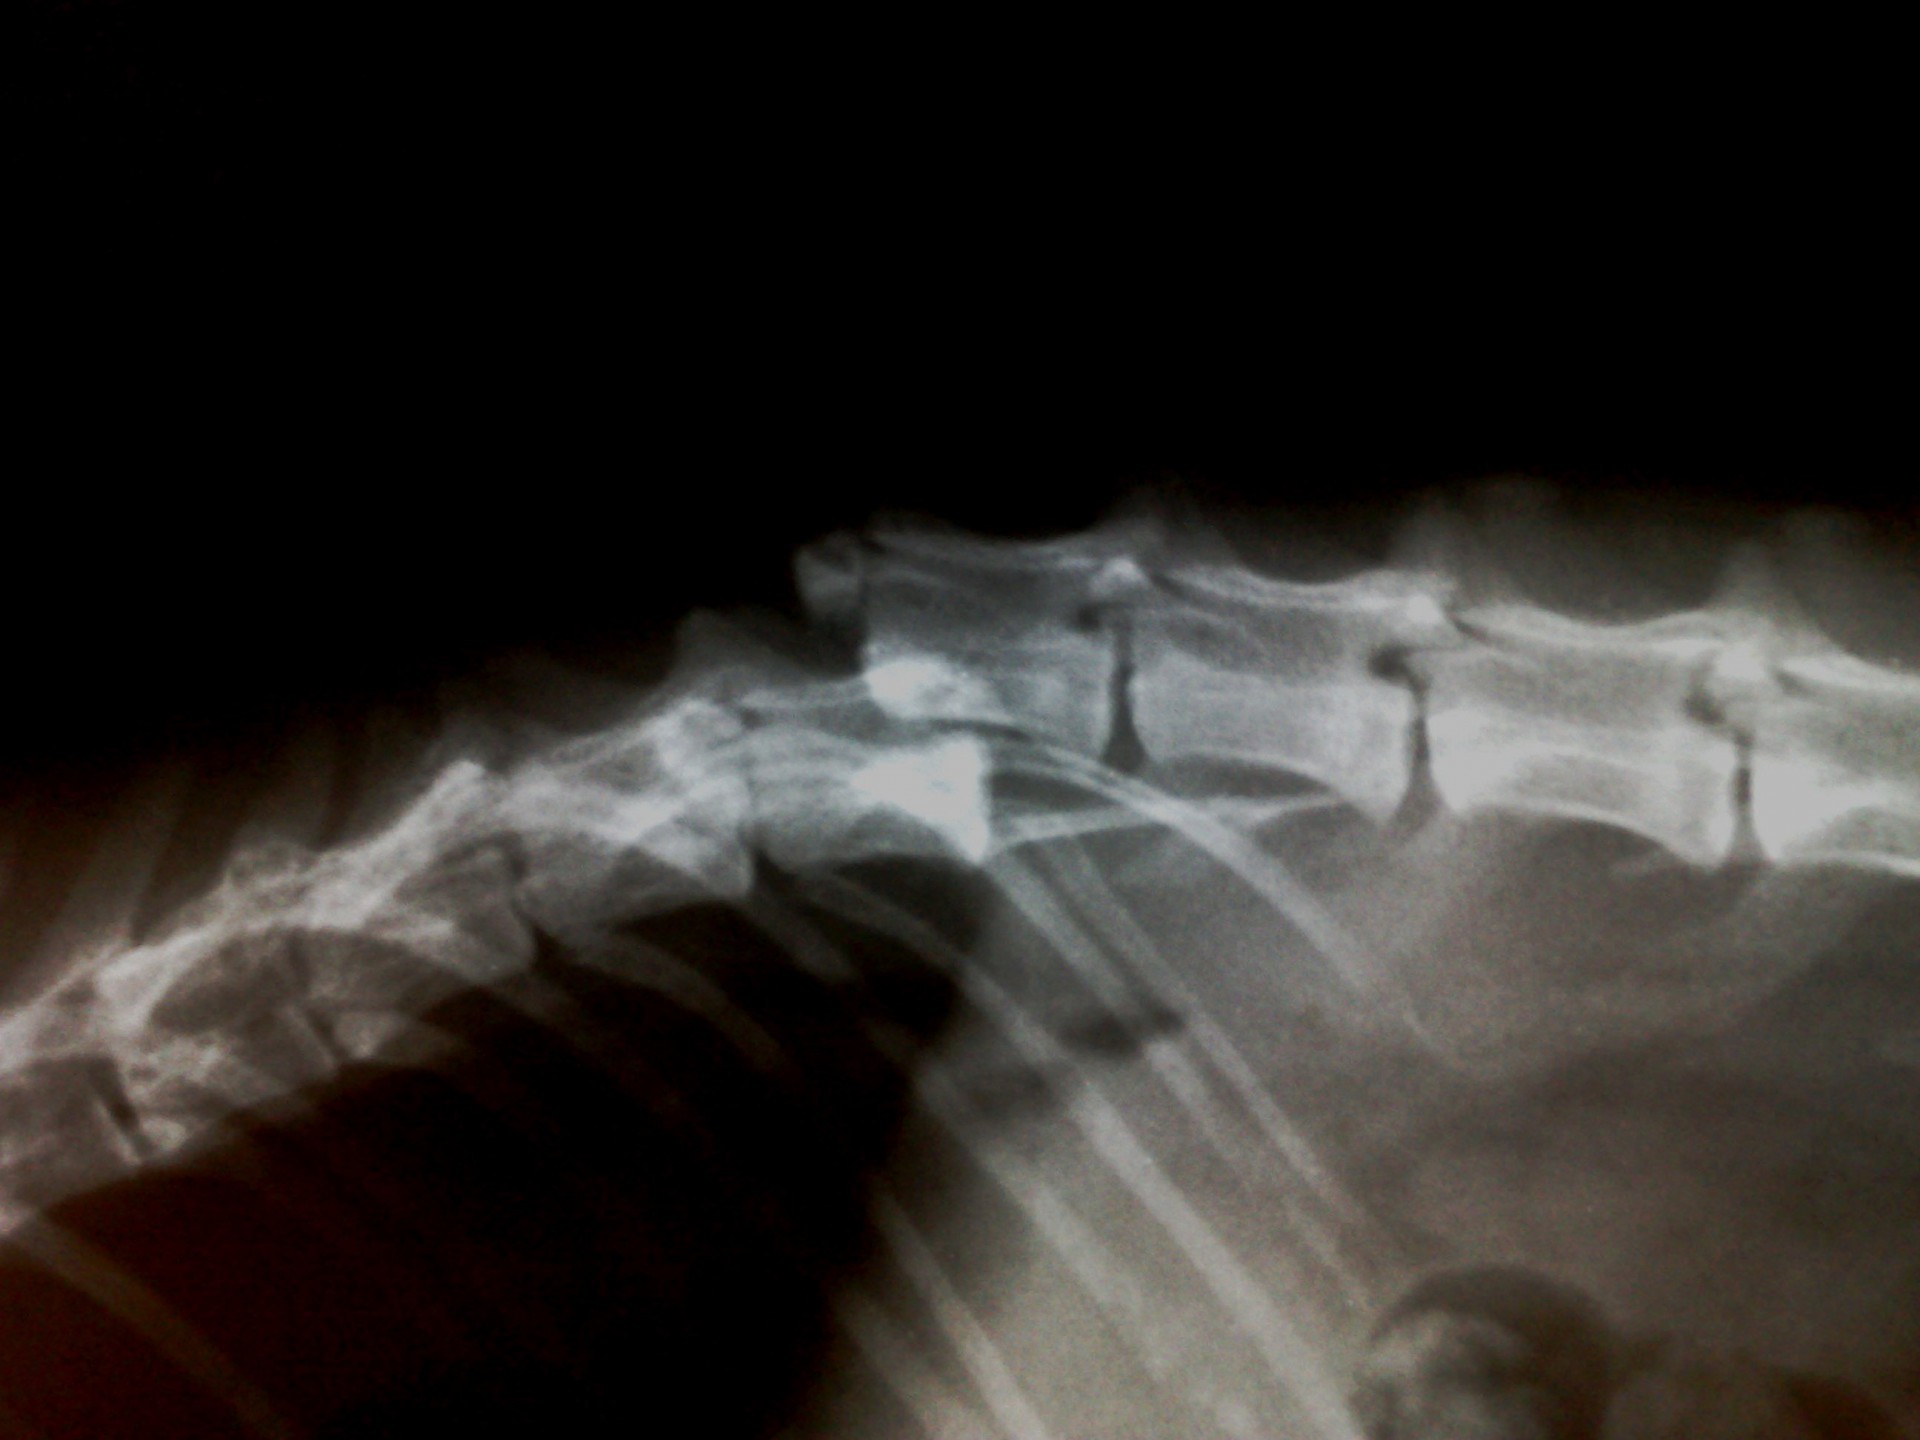

A gerinctörés diagnózisának felállítása komoly döntés elé állítja a tulajdonost és az állatorvost egyaránt. A gerinctörés következtében a gerincvelő minden esetben enyhébb-súlyosabb mértékben sérül. A gerincvelő sérülésének mértékét neurológiai vizsgálattal állapítjuk meg, de a diagnózis felállításához nélkülözhetetlen röntgen felvételről is már információt nyerhetünk a gerincvelő várható állapotáról. A tört végek egymáshoz képest történő kis mértékű elmozdulása esetén a gerincvelő körüli területek bevérzése miatt kialakult neurológiai tünetekkel találkozunk míg nagymértékű elmozdulásuk a gerincvelőt gyakorlatilag olló szerűen elnyírhatja. Így a natív röntgen felvételen a gerinccsatorna elmozdulásából már következtetést vonhatunk le a gerincvelőt ért sérülés mértékéről. A gerincvelő tényleges állapotáról azonban csak neurológiai vizsgálattal győződhetünk meg!

A gerinctörések műtéti ellátása kettős feladatot jelent: egyrészről a törés és elmozdulás következtében kialakult gerincvelő összenyomatást kell megszüntetni, másrészről a tört végeket kell adaptálni és eredeti állapotban - a további elmozdulás megakadályozása érdekében - rögzíteni. A műtéti ellátás során ezért minden esetben az érintett területen a gerinccsatorna felső csontos ívét eltávolítjuk (total laminectomia) így a gerincvelő sérülésének mértéke egyértelműen látható ill. a későbbi összenyomatása elkerülhető.